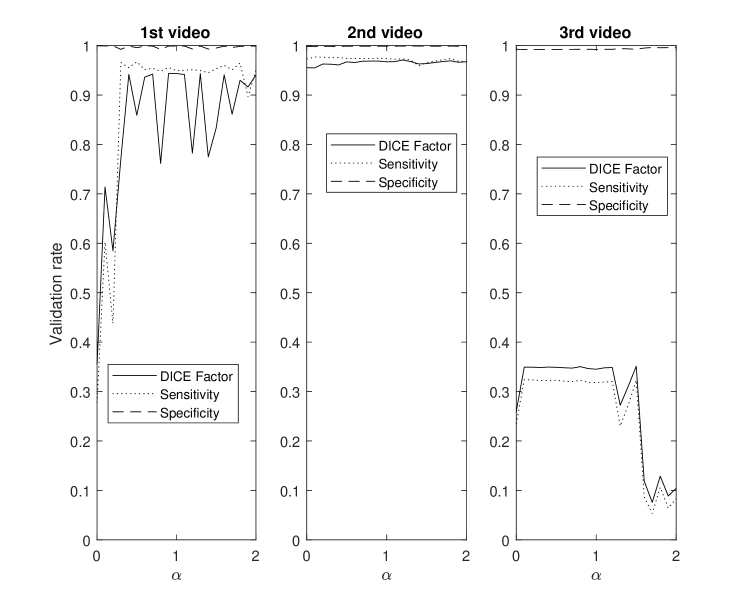

This section demonstrates the robustness of the algorithm for each parameter along with the relative importance of each parameter on the overall performance. This enables the identification and potential removal of weak features from the energy function in order to improve computational efficiency. For this study, the average DICE factor, sensitivity, and specificity of three different clips versus the initial parameters , , , , and are shown in Figs. 5-10. In the all of these figures, one can easily see that the specificity is always very close to one indicating a relatively small rate of .

The three test videos suggest setting to one supports optimal segmentation as shown in Fig. 5. Large values of result in excessive contour shrinking while small values reduce contour smoothness.